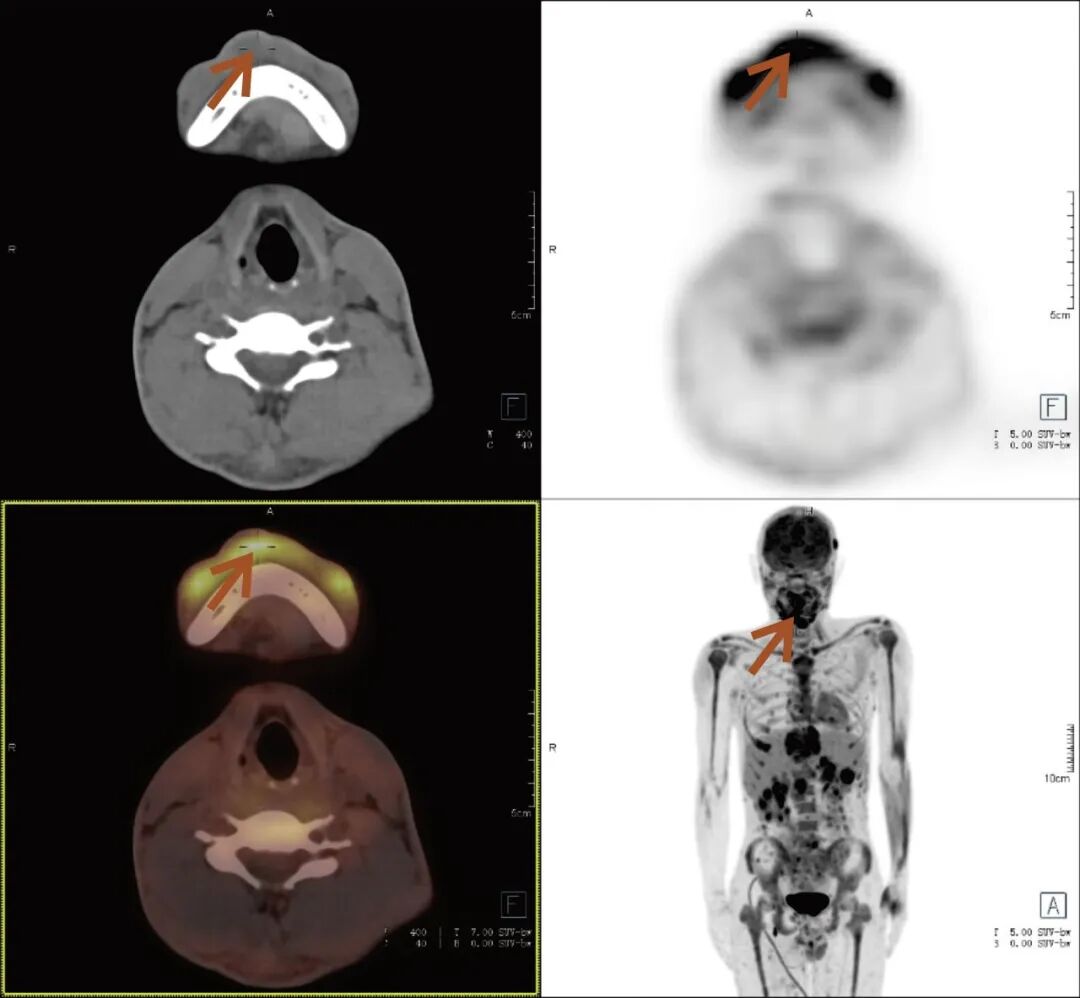

张先生(化名),因持续3个多月的腹痛、腰痛在外院就诊。初始CT检查发现其胸11椎体骨质破坏伴周围软组织肿胀,考虑为“脊柱结核”等感染性病变,并接受了中药治疗。然而,两个月后,张先生又出现了新的症状——牙痛。 经病理活检及免疫组化检查,最终确诊为极为罕见的Erdheim-Chester病。为全面评估这一可累及全身多系统疾病的侵犯范围、明确病灶活动性,并为制定精准治疗方案提供依据,张先生进行了全身PET/CT检查。 PET/CT检查图像: PET/CT检查结果: (1)中轴骨及四肢骨广泛FDG代谢活跃伴信号异常;其中胸10、胸11椎体病灶周围软组织增厚,累及邻近椎管内及双侧椎间孔、双侧胸膜,并与主动脉分界不清。 (2)全身皮下及肌层内多发结节及肿块,FDG代谢活跃;全身软组织广泛肿胀。 (3)鼻咽各壁增厚,顶后壁为著,FDG代谢活跃。 (4)甲状腺多发结节,FDG代谢活跃;双肾及胰腺多发结节及肿块,FDG代谢活跃;双侧阴囊内异常信号伴FDG代谢活跃; (5)左侧锁骨上窝、纵隔内(2L区、3A区)、降主动脉旁、左侧横膈前组、右侧腋窝、左肾周间隙、肠系膜区、双侧髂血管旁多发淋巴结,FDG代谢活跃; (6)心包局部呈结节状稍增厚,FDG代谢轻度活跃; 综上,结合临床,均考虑Erdheim-Chester病所致。 此次PET/CT不仅证实了已知的脊柱病变,更一次性揭示了临床尚未怀疑的、广泛存在于内脏、淋巴结及软组织的隐匿病灶,为疾病分期与治疗提供了决定性依据。